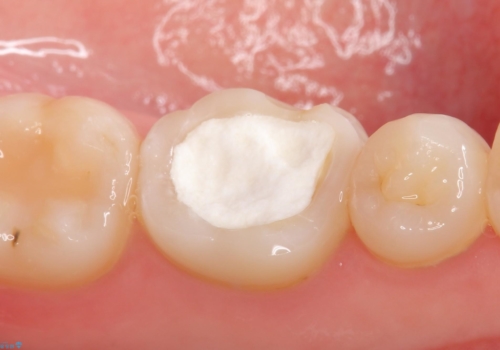

顕微鏡下で精密根管治療を行い、症状の緩解を確認後、オールセラミッククラウンによる補綴を行いました。

今回用いたオールセラミッククラウンはジルコニアフレームという白い素材の上にセラミックを盛っているため、審美性が非常に高いのが特徴です。

また、ジルコニアは人工ダイヤモンドの材料にも使われているほど高い強度を持っており、そのためオールセラミッククラウンは審美性だけでなく、奥歯やブリッジの補綴も可能とするクラウンです。